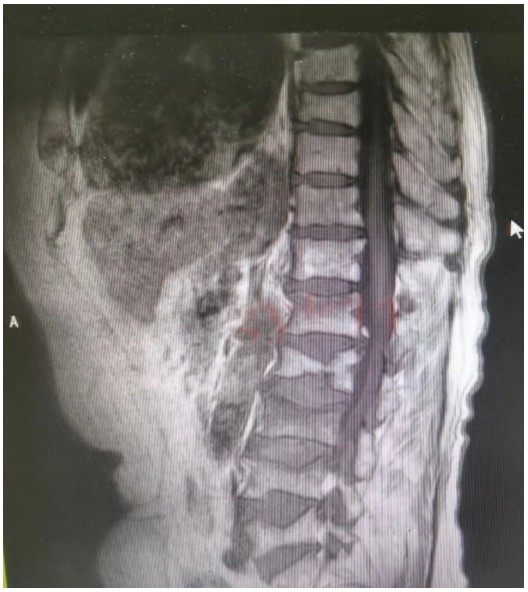

原來,89歲的占大爺因在家勞作時突發(fā)腰背部疼痛難忍、腰部無法直立,行走困難,在家臥床休息兩周后疼痛仍未減輕,于是來到衡陽市中心醫(yī)院脊柱外科就診。接診的盛凱醫(yī)師仔細查體結(jié)合磁共振檢查發(fā)現(xiàn),占大爺腰椎L1、L3、L4有椎體壓縮骨折,診斷為腰椎體壓縮骨折、重度骨質(zhì)疏松癥。錢軍博士團隊結(jié)合對病人多椎體的骨折做出了細致的評估,經(jīng)過認真分析研究,決定為患者實施腰椎體壓縮性骨折經(jīng)皮穿刺椎體成形術(shù)(PVP)。手術(shù)當天,醫(yī)師團隊在C-臂監(jiān)視器透視下,分別定位L1、L3、L4雙側(cè)椎弓根位置,以標記穿刺點為中心做3mm切開,在透視下注入骨水泥,再次透視見骨水泥位置良好,順利完成手術(shù)。